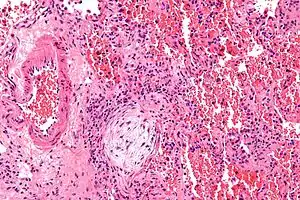

![]() | |

| Micrograph showing a Masson body (off center left/bottom of the image – pale circular and paucicellular), as may be seen in cryptogenic organizing pneumonia. The Masson body plugs the airway. The artery associated with the obliterated airway is also seen (far left of the image). H&E stain. | |

Organizing pneumonia is usually preceded by some type of lung injury that causes a localized denudation or disruption in continuity of the epithelial basal laminae of the type 1 alveolar pneumocytes that line the alveoli.[7] This injury to the epithelial basal lamina results in inflammatory cells and plasma proteins leaking into the alveolar space and forming fibrin, resulting in an initial fibroblast driven intra-alveolar fibroproliferation.[7] The fibroblasts differentiate into myofibroblasts and continue to form fibrosis resulting in intra-alveolar fibroinflammatory buds (Masson's Bodies) that are characteristic of organizing pneumonia.[7] These Masson's bodies consist of inflammatory cells contained in an extracellular matrix consisting of type I collagen, fibronectin, procollagen type III, tenascin C and proteoglycans.[7] Angiogenesis , or the formation of blood vessels, occurs in the Masson's bodies and this is driven by vascular endothelial growth factor.[7] Remodeling occurs, resulting in the intra-alveolar fibroinflammatory buds (Masson's Bodies) moving into the interstitial space and forming collagen globules that are then covered by type 1 alveolar epithelial cells with well developed basement membranes. These type 1 alveolar epithelial cells (pneumocytes) then proliferate, restoring the continuity and function of the alveolar unit.[7] This process is in contrast to the histopathologic changes seen in usual interstitial pneumonia where extensive fibrosis and inflammation occur leading to fibroblastic foci to form in the alveolar spaces resulting in obliteration of the alveolar space, scarring and significant damage to lung architecture (the alveoli).[7]

Biopsy findings in patients with organizing pneumonia consist of loose connective tissue plugs involving the alveoli, alveolar ducts and bronchioles. The loose connective tissue plugs occupying the alveolar spaces often connect to other connective tissue plugs in nearby alveoli via the pores of Kohn creating a characteristic butterfly pattern on histology.[7] There is usually minimal to no interstitial inflammatory changes in biopsies of organizing pneumonia.[7]

Histologically, cryptogenic organizing pneumonia is characterized by the presence of polypoid plugs of loose organizing connective tissue (Masson bodies) within alveolar ducts, alveoli, and bronchioles.